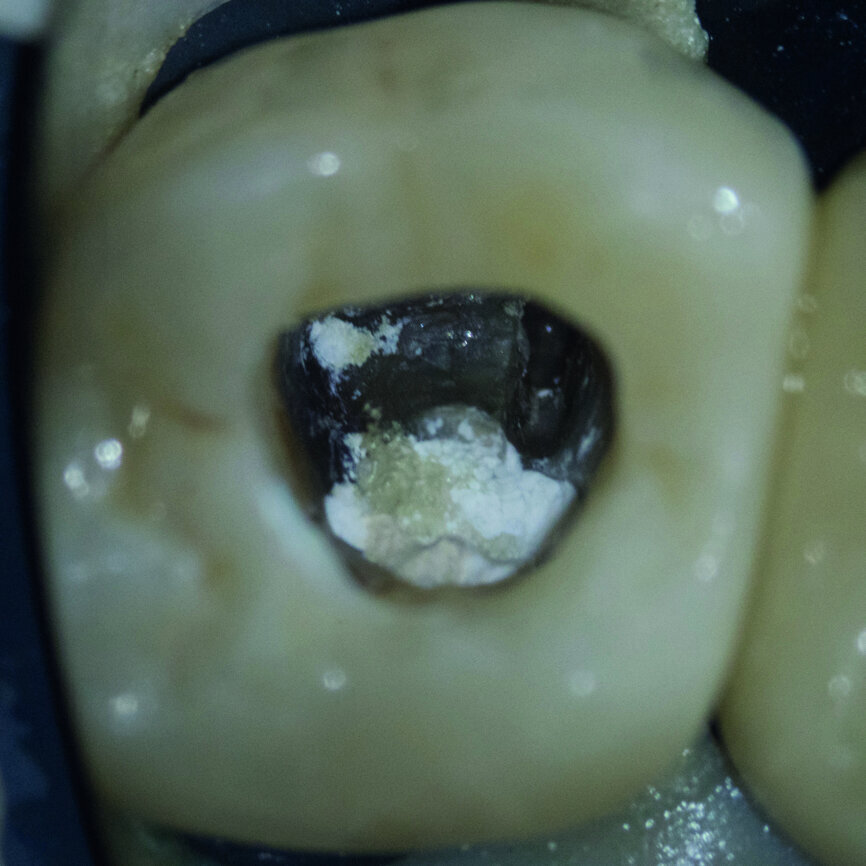

Fig. 3 : La perforation a été fermée avec un ciment hydraulique à base de silice.

Fig. 6 : Le ciment hydraulique à base de silice après sa prise complète.

Fig. 7 : L’excès de ciment a été éliminé autant que possible.

Au cours de la deuxième visite, l’excès de ciment hydraulique à base de silice a été éliminé autant que possible (Figs. 6 et 7) puis la dentine a été obturée au moyen de G-Premio BOND avant une désinfection par NaClO, selon le protocole de ≪ scellement endodontique immédiat (IES) ≫,1 qui est similaire au protocole de scellement dentinaire immédiat (IDS) (Fig. 8). Cet adhésif universel doit être sèche à l’air sous pression élevée. Il est idéal pour les cavités endodontiques profondes car il n’y a pas d’accumulation de l’adhésif sur le fond cavitaire.